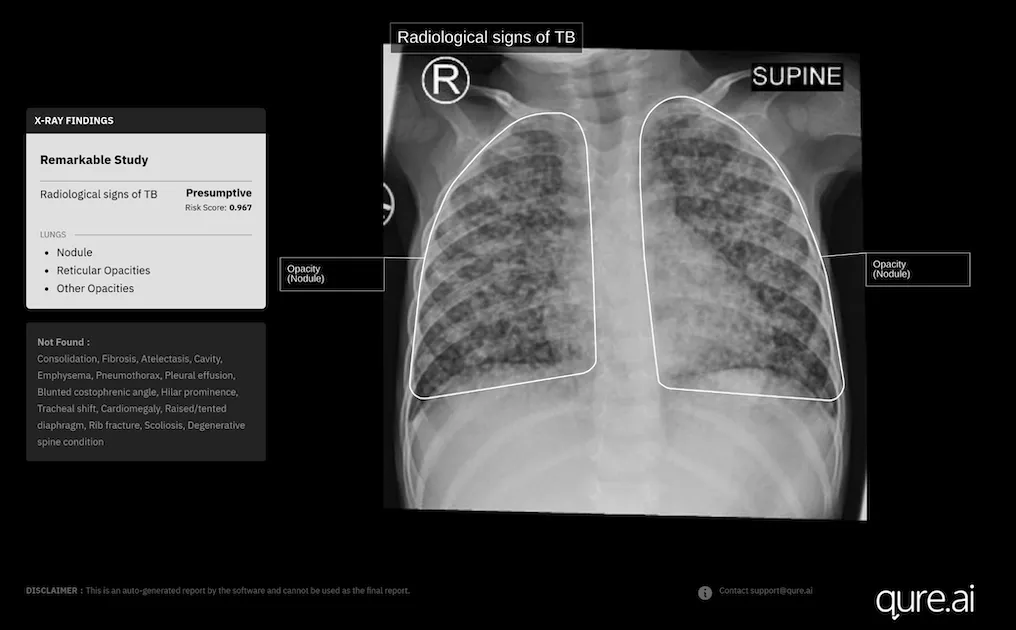

Photo courtesy of Qure.ai

Indian medical imaging AI company Qure.ai has secured new approval in Europe for the expanded use of its chest X-ray analysis AI tool to diagnose paediatric tuberculosis in toddlers.

It has recently received a new CE Mark under the European Union's Medical Device Regulation for the use of its AI-powered chest X-ray software, qXR, in children aged 0-3 years.